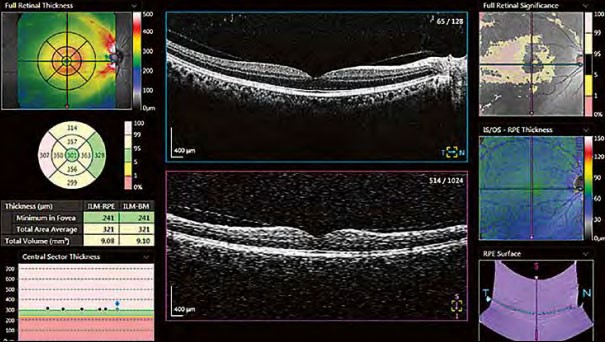

Надійне розпізнавання 10 шарів

Xephilio OCT-A1 компанії Canon може автоматично виявити та розрізнити 10 шарів сітківки, включаючи мембрану Бруха (BM) - завдяки чудовій якості зображення та розподільчій здатності.

Макула

Система забезпечує детальний аналіз товщини сітківки за допомогою порівнянь з нормативними базами даних, сітками ETDRS, різними таблицями та 3D-візуалізаціями.